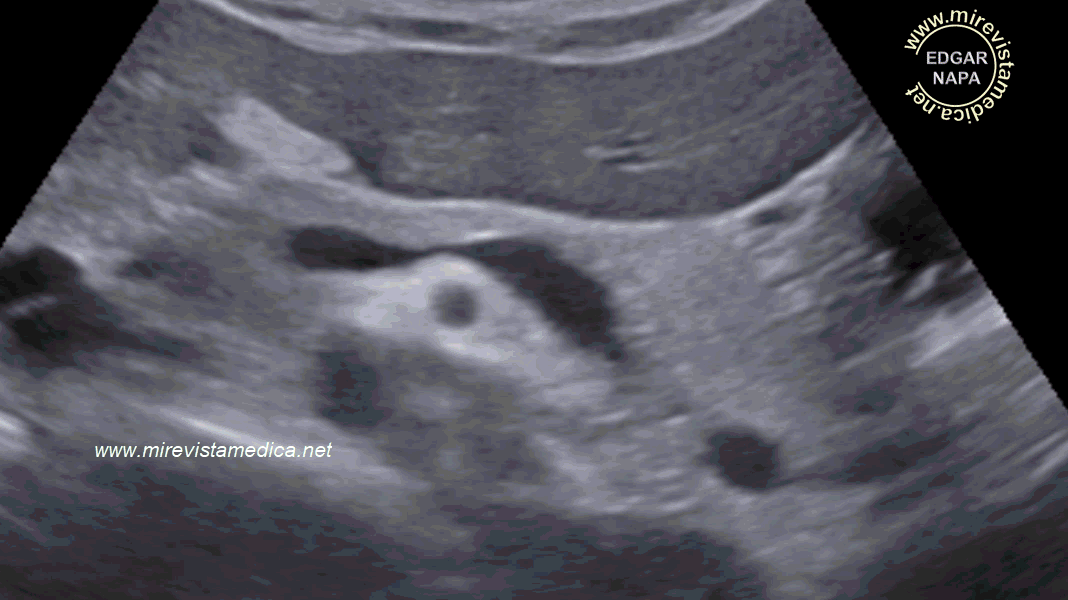

El parénquima pancreático presenta ecos finos distribuidos de manera homogénea, no evidenciándose lesiones focales,

Los contornos de la silueta pancreáticas son circunscritos, liso (en algunas ocasiones lobulado).

En la imagen ecográfica,

vista transversa, se observa parcialmente la silueta pancreática, no se observa la cola, por interposición de asas intestinales.